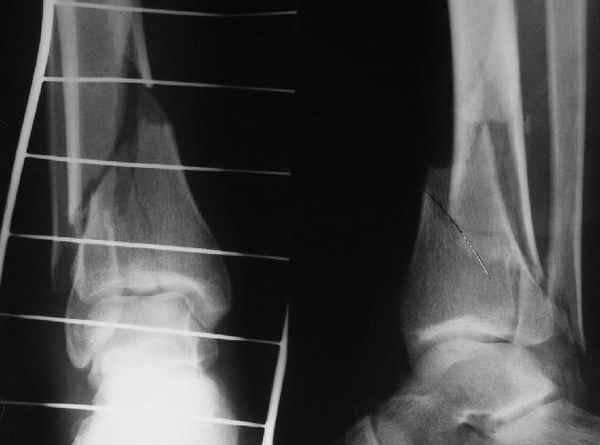

I would suggest to fix the fibular fracture at the very beginning and under fluoroscopical control and axial traction try to restore articular surface stabilizing percutanously by K wires and cannulated screws, type of external fixation to be used is up to your preference.

A propos fibular fixation if one is eager to stabilize it separately. In the fracture pattern a way of closed fixation by V-shaped stressed wire (advanced by colleagues from Moscow, prof. Lazarev A.F. et al.) must be excellent. We use indirect closed reduction by the external fixator. Example attached, that fibular fracture is even more suitable for plating but the wire did the job.

Отправитель: Djoldas Kuldjanov, M.D. 16 Сентябрь 2004, 21:34

Pilon fracture: